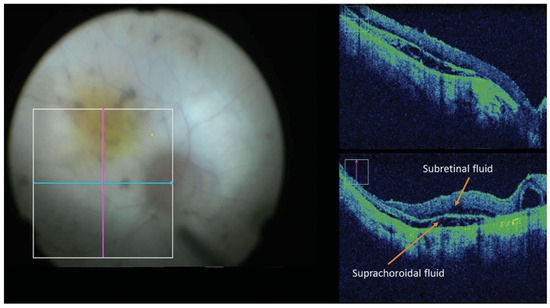

- Gregori, N.Z.; Lam, B.L.; Davis, J.L. Intraoperative Use of Microscope-Integrated Optical Coherence Tomography for Subretinal Gene Therapy Delivery. Retina 2019, 39 (Suppl. S1), S9–S12. [Google Scholar] [CrossRef]

- Vasconcelos, H.M.; Lujan, B.J.; Pennesi, M.E.; Yang, P.; Lauer, A.K. Intraoperative Optical Coherence Tomographic Findings in Patients Undergoing Subretinal Gene Therapy Surgery. Int. J. Retin. Vitr. 2020, 6, 13. [Google Scholar] [CrossRef]

- Valikodath, N.G.; Li, J.D.; Raynor, W.; Izatt, J.A.; Toth, C.A.; Vajzovic, L. Intraoperative OCT-Guided Volumetric Measurements of Subretinal Therapy Delivery in Humans. J. Vitreoretin. Dis. 2024, 8, 587–592. [Google Scholar] [CrossRef] [PubMed]